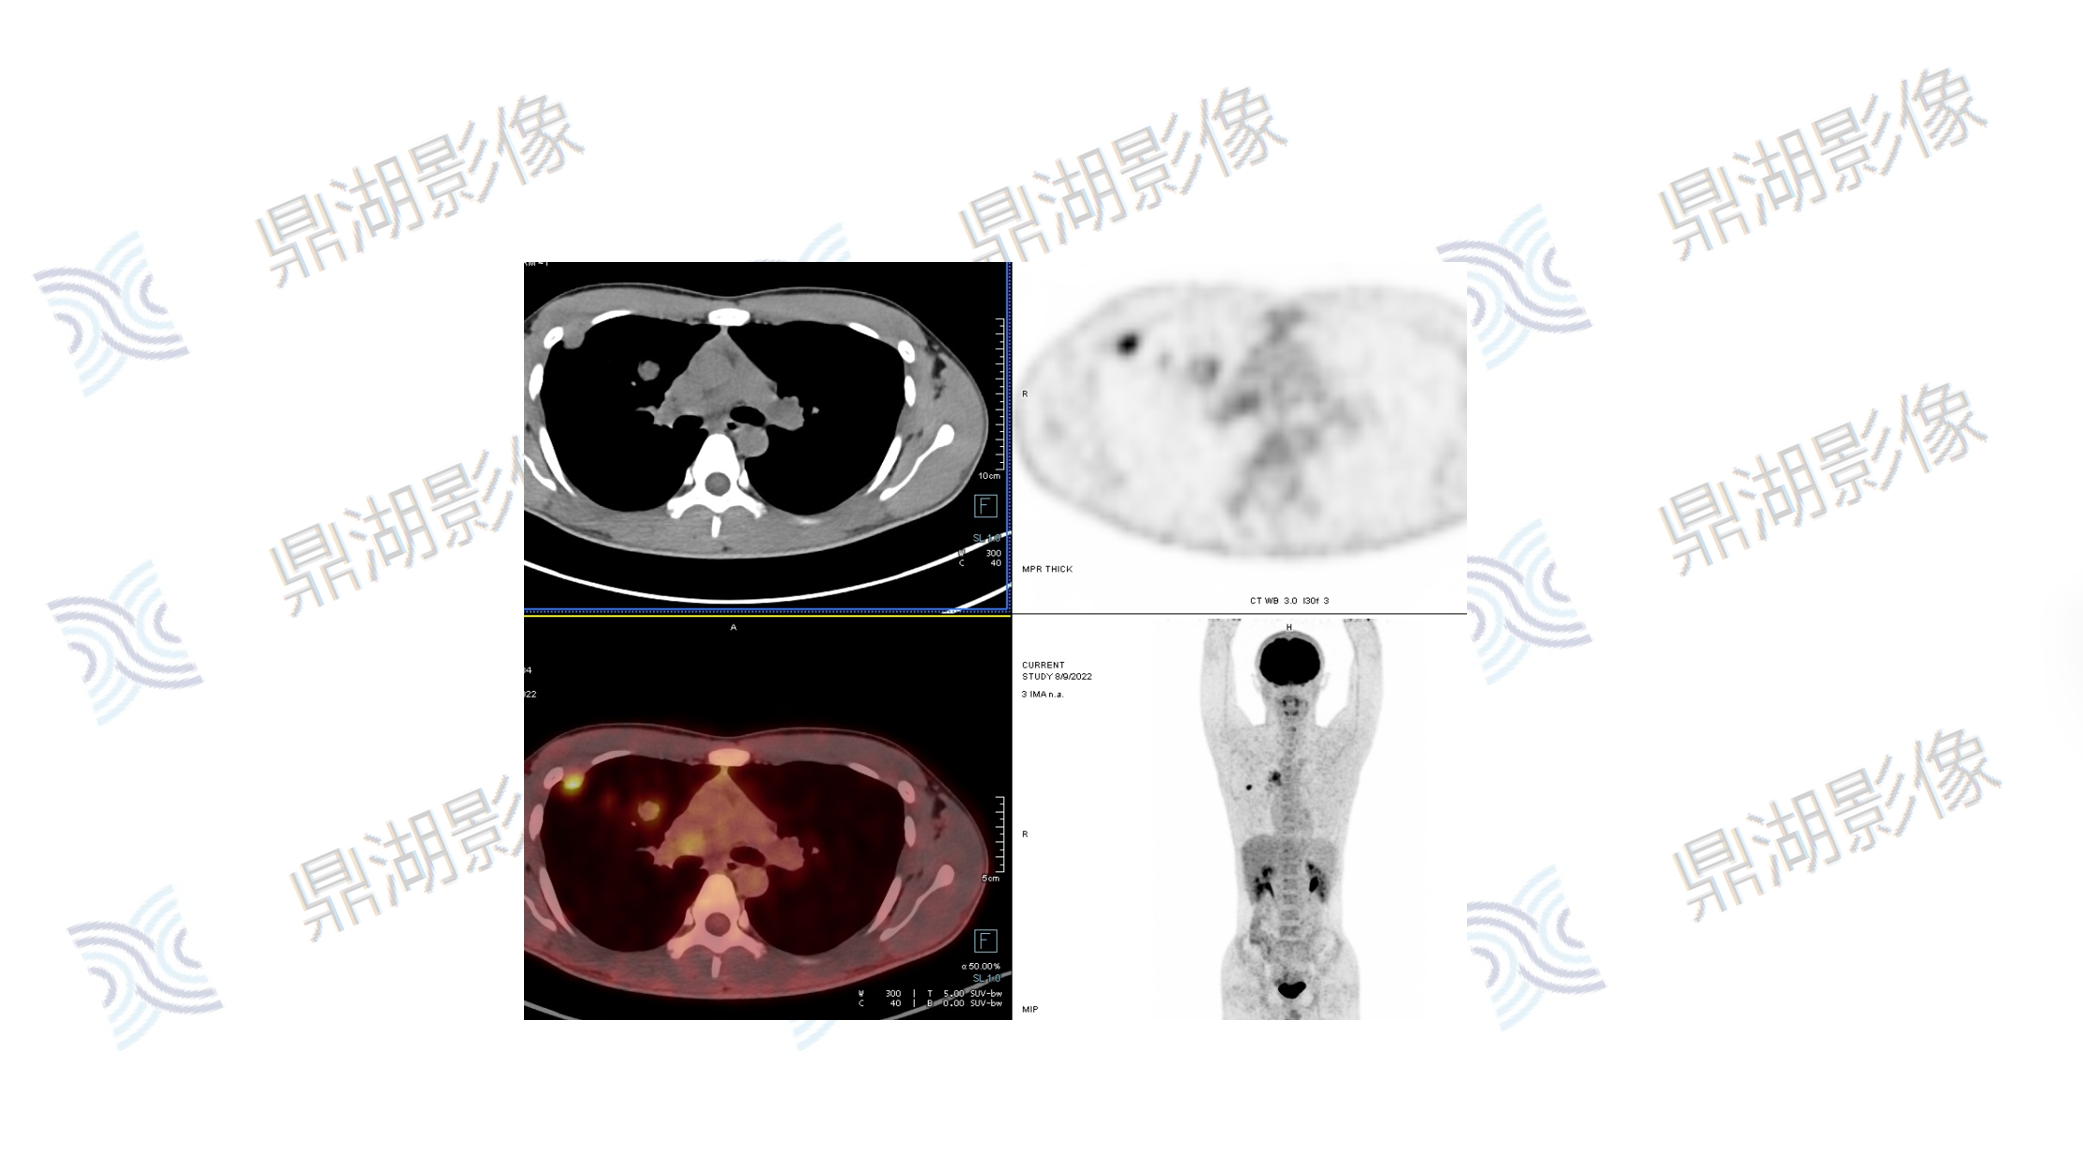

肺动脉内膜肉瘤

性别:男

年龄:20

主诉:咳嗽3月

病例分析